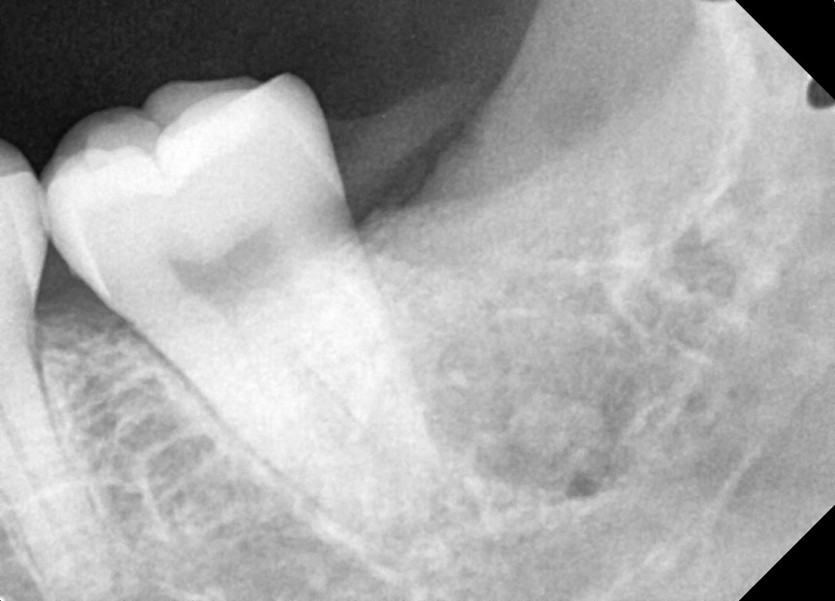

#28, 38 사랑니 발치

구강 외과 전문의가 당일 발치했습니다.